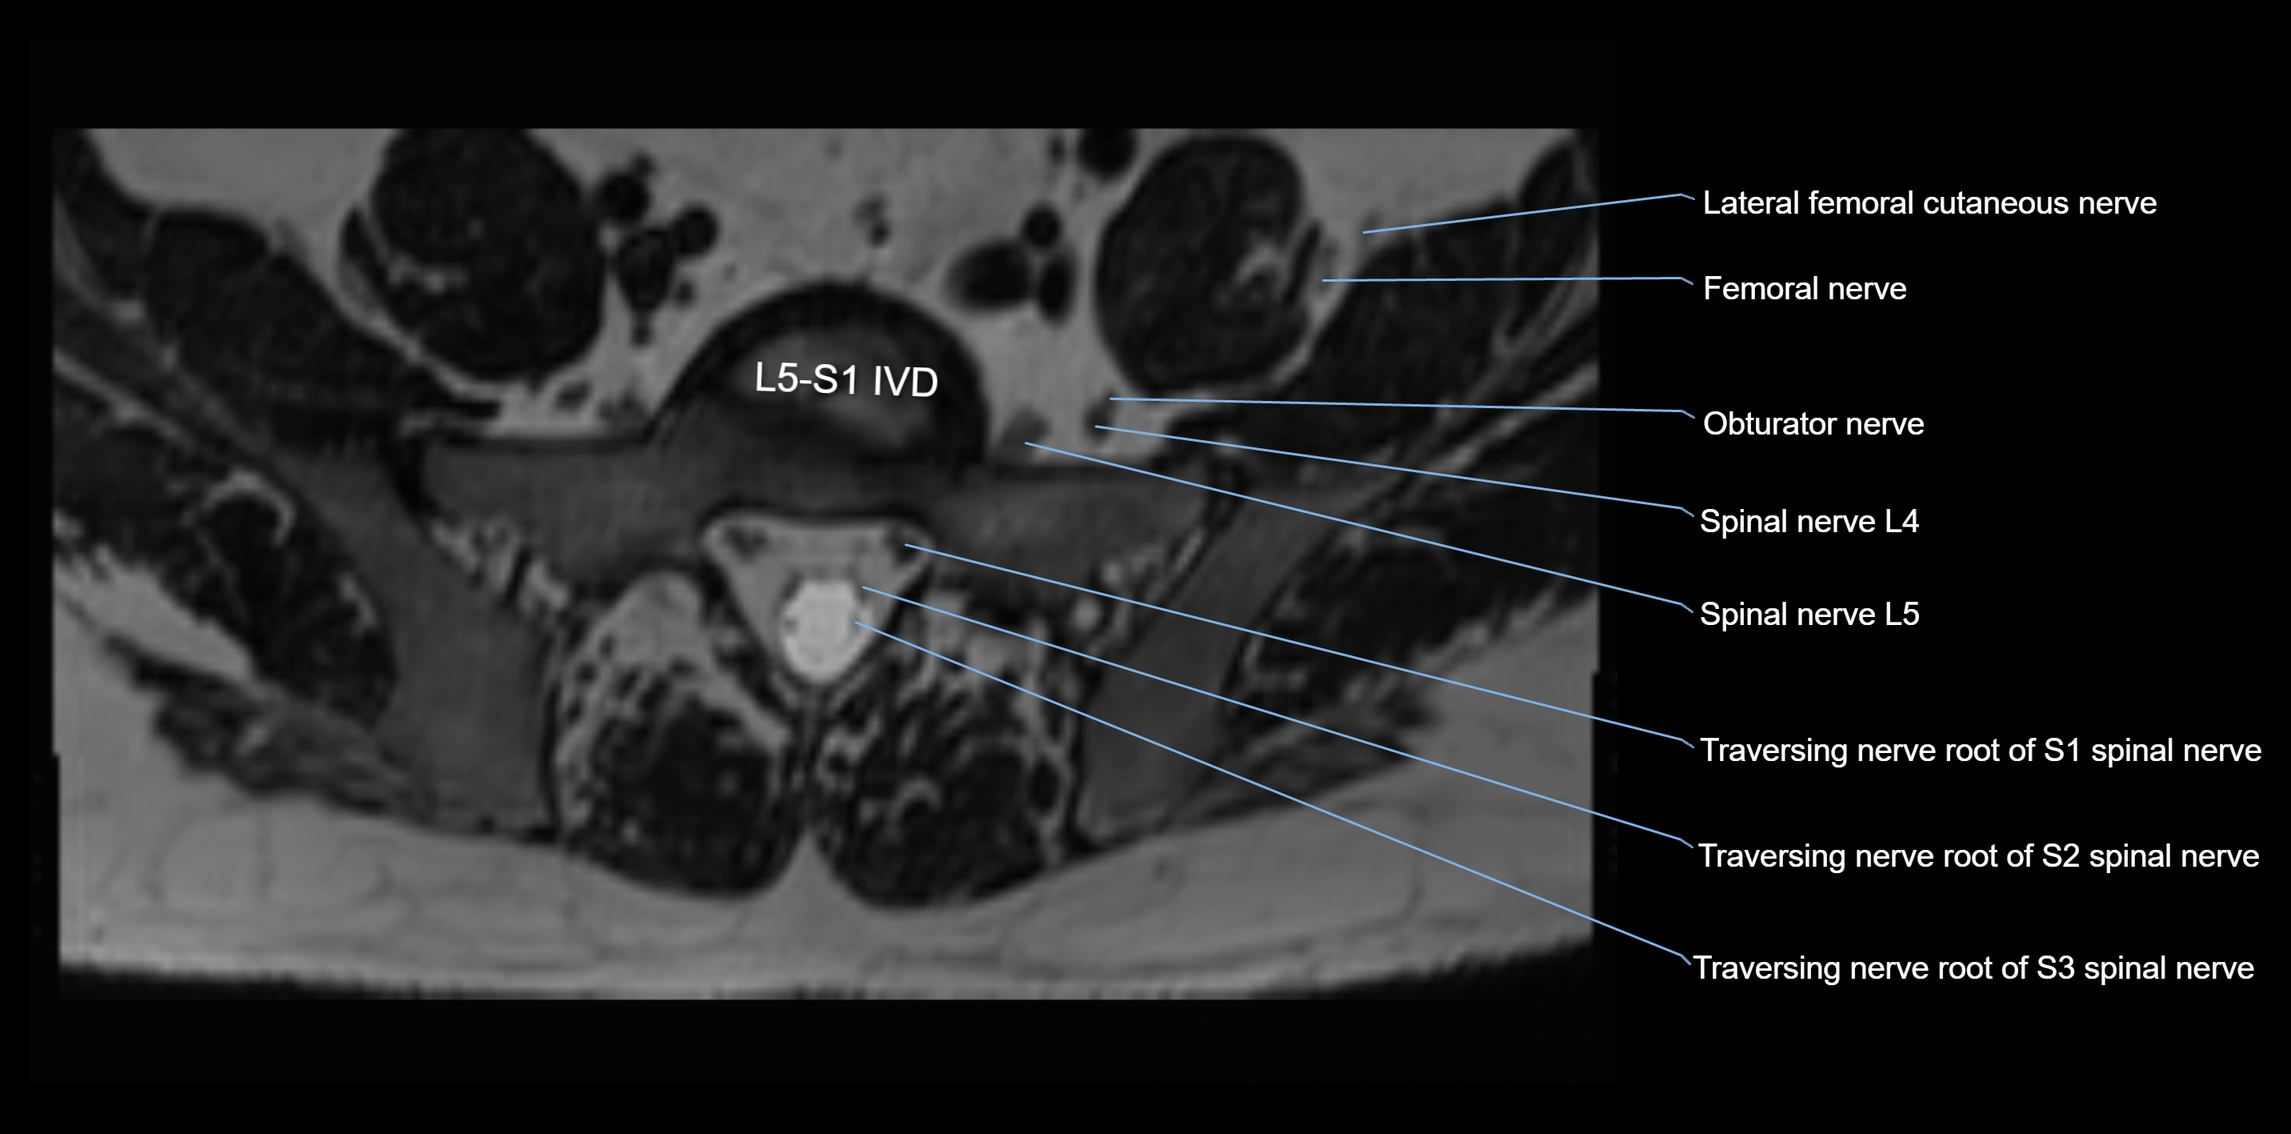

MRI image

image